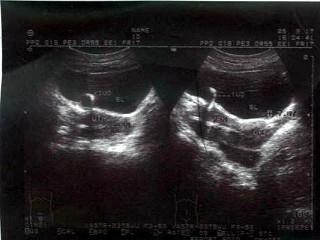

问题 女,已放置节育器;腹痛,镜下血尿,超声显像如图,最可能的诊断为?(?)

选项 A.膀胱肿瘤 B.膀胱结石 C.节育器异位膀胱 D.右输尿管末端囊肿 E.以上都不是

答案 C